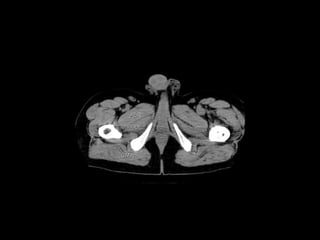

Radiographers use medical imaging equipment like X-rays and MRIs to produce images of patients' internal structures and organs. They are responsible for positioning patients, operating scanning machines, and ensuring quality images. Radiographers must have strong attention to detail, excellent communication skills, and the ability to work well under pressure to accurately capture anatomical features and diagnose any abnormalities.